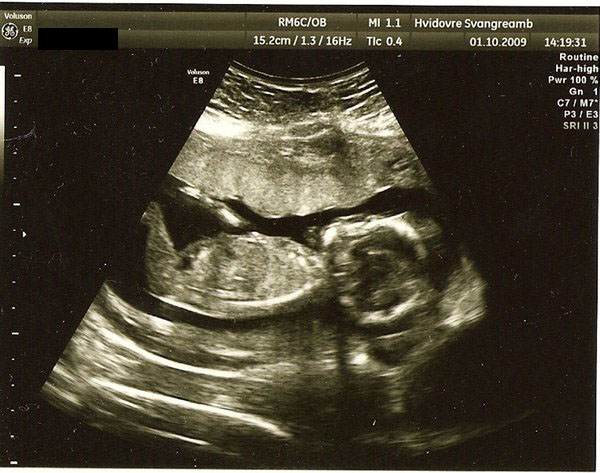

De første 2 billeder er fra nakkefoldescanningen (i uge 13), det næste er fra misdannelses scanningen i uge 20 og det sidste (og dårligeste) er fra den første hjerte scanning i uge 26.